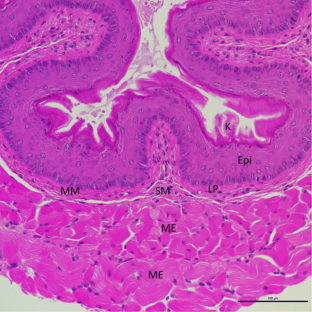

Fig. 1

Fig. 2

49. • Takahashi T, Asano Y, Sugawara K, Yamashita T, Nakamura K, Saigusa R, et al. Epithelial Fli1 deficiency drives systemic autoimmunity and fibrosis: possible roles in scleroderma. J Exp Med. 2017;214(4):1129–51. https://doi.org/10.1084/jem.20160247. This is the first SSc mouse model reporting an esophageal phenotype.